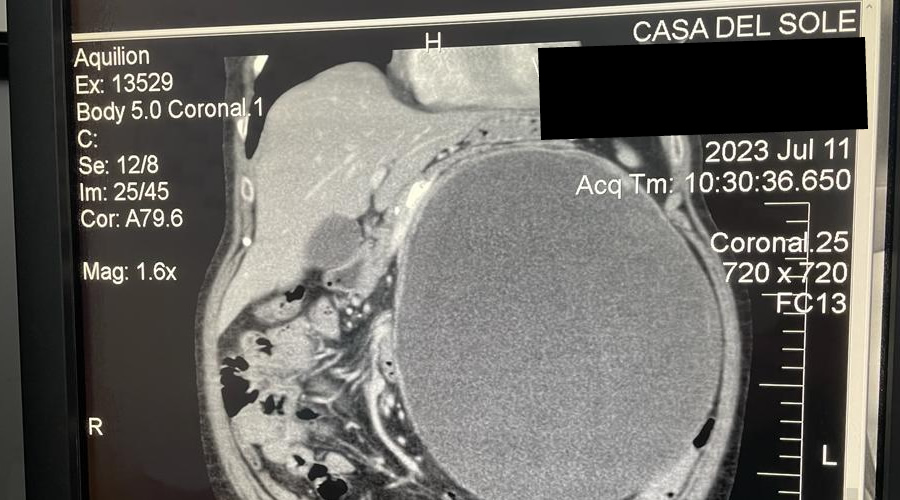

Giovanni Baiano “la signora è giunta alla nostra osservazione per una sintomatologia sub occlusiva

lamentando difficoltà alla evacuazione. Sottoposta a tac addome si è evidenziata una enorme massa

addominale che di fatto aveva spostato tutto l’intestino verso il lato destro dell’addome stesso ed il

rene sinistro in basso in prossimità della vescica. Per tale motivo l’abbiamo sottoposta ad intervento

chirurgico della durata di circa 2 ore e mezzo con il quale abbiamo asportato l’enorme

neoformazione: diametro 28 cm peso 3,8 chili. Abbiamo ovviamente utilizzato tecnologie

all’avanguardia tipo bisturi ad ultrasuoni e suturatrici endogiavascolari.